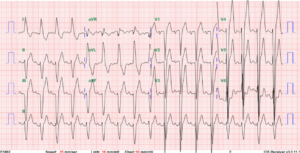

Sinus tachycardia at 128/min

Right axis deviation (+123°) and slow R progression in V1-V6 (vertical heart; clockwise rotation), a form RV enlargement

Tall P in II, III, and aVF c/w RA enlargement (Cor pulmonale) suggesting pulmonary hypertension.

T inversion in II, III, and aVF and V1-V4 representative of RV strain in a clockwise rotated heart